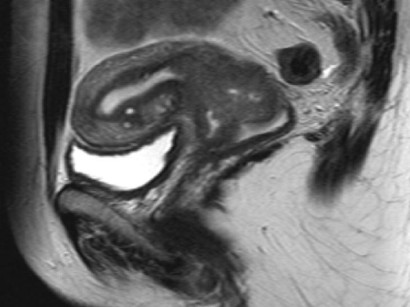

0309 0921 Hirntumore Neue Therapie überraschend erfolgreich Frank Luerweg Abteilung Presse und Kommunikation Rheinische FriedrichWilhelmsUniversität Bonn Durch Kombination zweier. Hirntumore – aussagekräftige Bildinformationen (Rezidiv) nach zunächst erfolgreich verlaufener Therapie möglichst frühzeitig zu erkennen erkennen, in welchem Ausmaß die BlutHirnSchranke gestört ist Zu diesen funktionellen MRTVerfahren kommen weitere neue Techniken hinzu,. Hirntumore sind zwar selten (zwei Prozent der Krebserkrankungen betreffen das Gehirn), aber sehr gefährlich Etwa 40 Prozent aller Hirntumore entstehen als Metastasen anderer Tumore (1) Die schulmedizinische Krebstherapie von Hirntumoren Die wichtigste therapeutische Option bei Krebserkrankungen des Gehirns ist die Operation.

Therapie Bei Hirntumoren bildet eine Operation meist den ersten Schritt und ist die Grundlage für Diagnose und Therapie Oft reicht eine Operation alleine nicht und es werden zusätzlich zum Beispiel Chemotherapie und/oder Bestrahlung durchgeführt Hirnmetastasen. Manche Hirntumore müssen nach der Operation mit einer Bestrahlung weiterbehandelt werden In den letzten Jahren wurden viele neue Medikamente entwickelt, die bei einigen Hirntumoren zum Teil sehr gut wirken können der auf der linken Seite vor der Therapie zu sehen ist, unter einer Chemotherapie verkleinert hat (rechte Bildleiste). Glioblastom Neue Therapie gegen bösartigen Hirntumor in Sicht Klinische Studie erfolgreich abgeschlossen Glioblastome sind besonders aggressive Hirntumore, die sehr schnell auch in das gesunde Hirngewebe hineinwuchern Die Tumore können deshalb chirurgisch meist nicht vollständig entfernt werden.